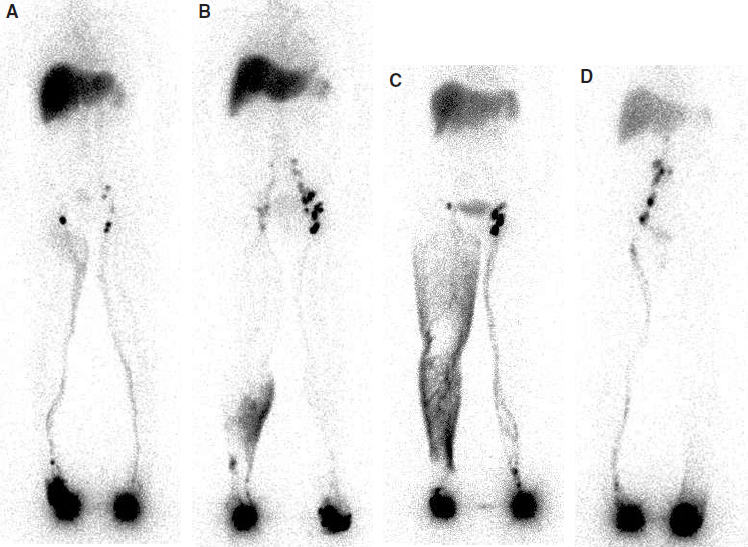

LSG is a functional study to complement the anatomic information on the lymphatic system gleaned from other studies, such as phlebography or venography. It offers not only an anatomic study of the subaponeurotic lymphatic vessels but also a functional assessment. One of the criticisms of LSG is that the anatomic definition of the images is very poor, and this is true in the context of surgical planning. Both MRI (see Chapter 28) and ICG lymphangiography (see Chapter 27) provide much better information on detailed anatomy. However, neither of these studies is as widely available as LSG. With LSG, an evaluation can be done in both qualitative and quantitative assays, and the quantitative measurements in particular can give functional imaging of the lymphatic transport capacity 30 – 33 (Fig. 26-3).

Although LSG is considered a “functional” imaging modality, it delivers comprehensive and consistent images, visualizing various structural and functional changes in lymphatic flow dynamics. LSG produces dynamic images of lymphatic transport and the peripheral and central lymphatic structures and function. Its transport index score 36 allows semiquantification of peripheral lymphatic radiotracer transport. Delayed imaging shows lymph node uptake, albeit without the detailed structural information seen with conventional lymphography.

LSG also has special merit in assessing the efficacy of medicines, surgery, and physical means to facilitate lymph movement or reduce lymph formation before and after treatment. Images of truncal lymph transport and draining nodes can be routinely obtained for follow-up studies to document functional changes in lymphatic dynamics (Fig. 26-4).